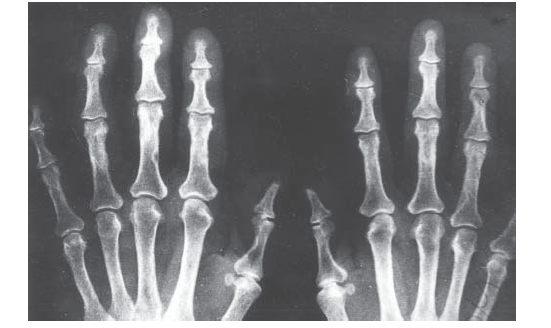

8.4 сурет.Біріншілік гиперпаратиреоз кезіндегі қол ұшының рентгенограммасы: саусақтардың субпериостальды резорбциясының белгілері

4. Сүйектік өзгерістер: остеопороз, хондрокальциноз; ауыр БГП: субпериостальды резорбция, қол, аяқ саусақтарының акроостеолизі (8.4 сурет), қаңқа деформациясы, сүйектердің патологиялық сынықтары (8.5 сурет), кисталар (жылауық), алыпжасушалық ісіктер және эпулидтер (кисталық түзілістер).